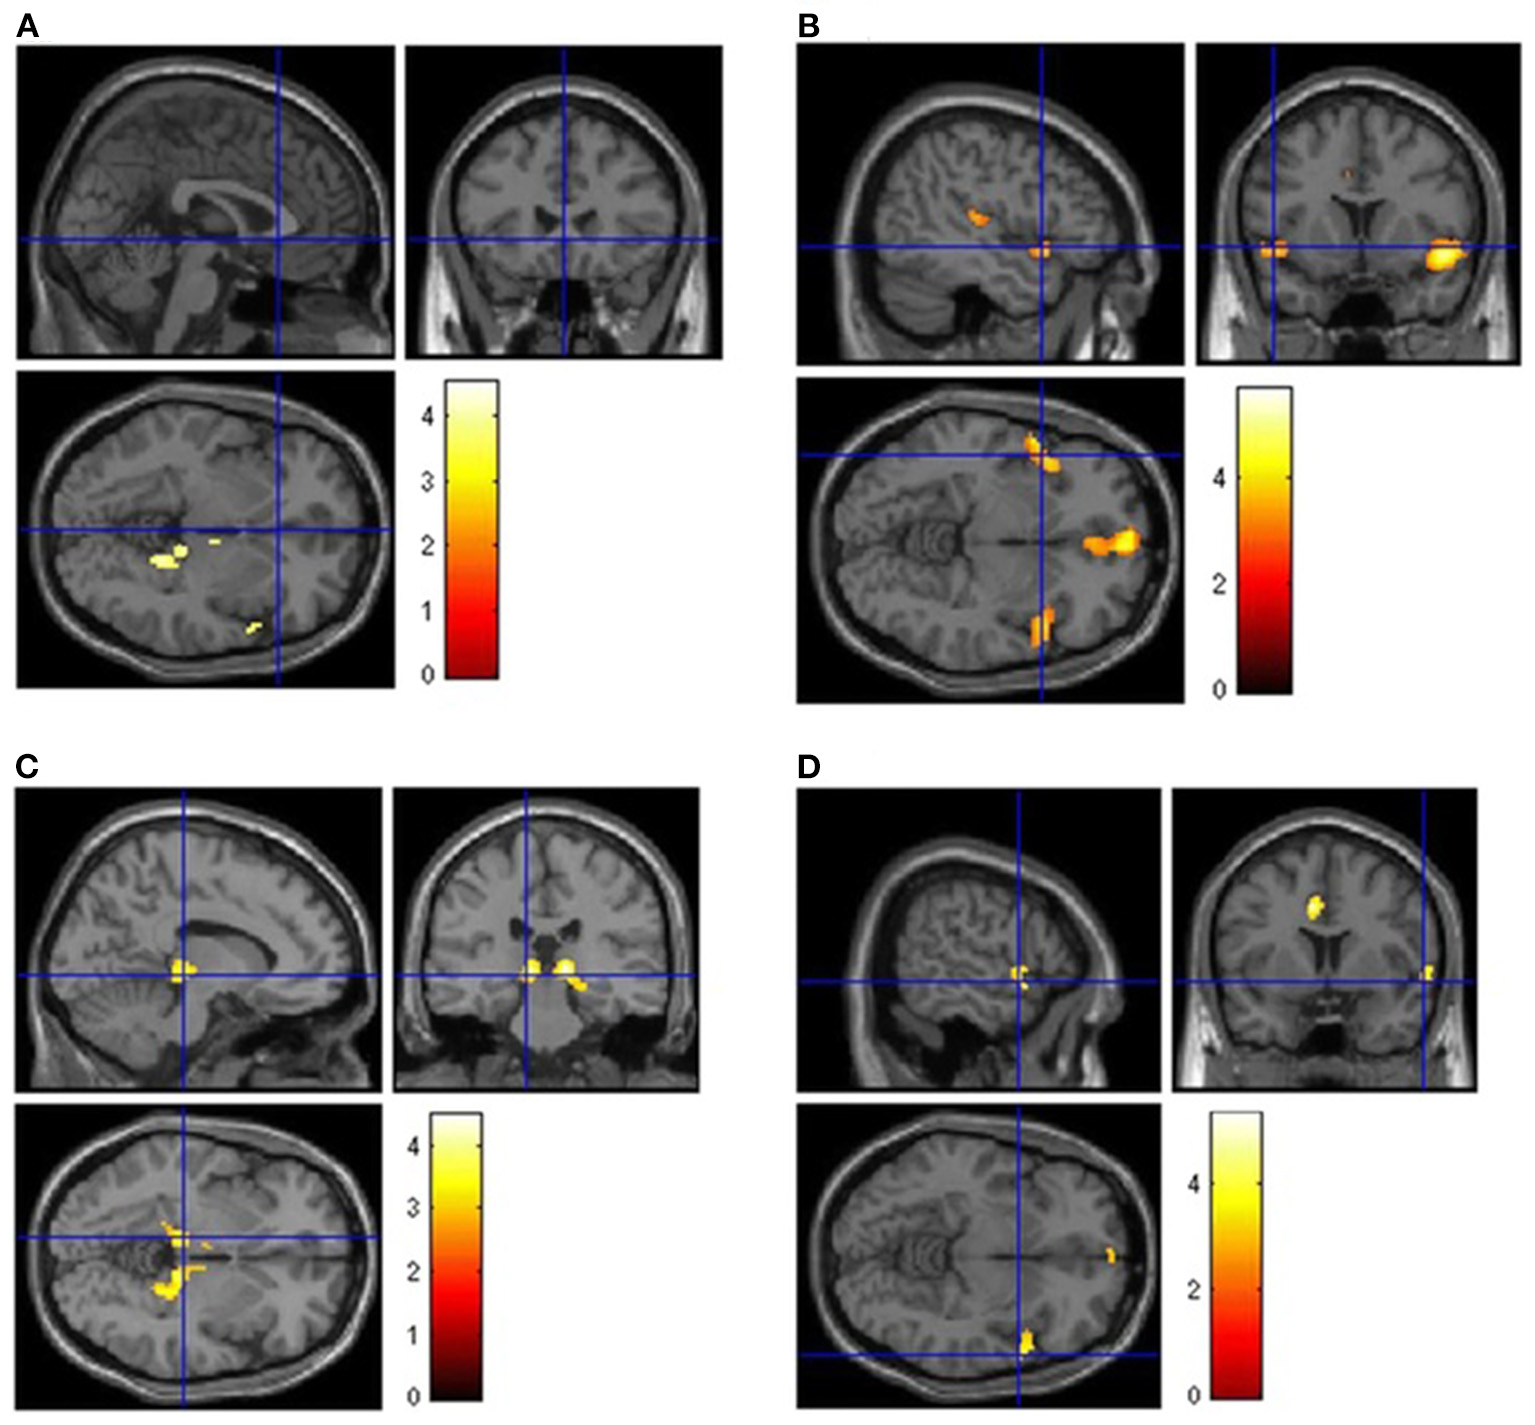

According to certain studies, patients with Post COVID-19, who have chronic functional problems, have 18F-FDG-PET hypometabolism in several cerebrum areas (45–48). After analyzing the 18F-FDG cerebral PET of patients with PCNS, with a scientifically verified diagnosis of SARS-CoV-2 disease and chronic functional symptoms at least 3 weeks after the first infection, scientists discovered hypometabolism in: the bilateral orbital gyrus which contains the olfactory gyrus, the right parahippocampal gyrus, the right temporal lobe e.g., amygdala, hippocampus, and thalamus, the bilateral cerebellum and the bilateral pons/medulla brainstem (45–48) (Figures 2, 3). Furthermore, this hypometabolism was linked to the patients' problems e.g., memory and cognitive dysfunction, sleep disturbances and pain (45–47). Moreover, a new research with 18F-FDG-PET demonstrated the neurological long-term consequences of COVID-19 (49). The imaging revealed abnormal findings in more than 66% of the individuals, most of whom presented fronto-parietal hypometabolism (49). In conclusion, the 18F-FDG-PET data demonstrated above suggests that the frontal, temporal, and parietal lobes are sensitive to SARS-CoV-2 infection (45–49).

Figure 2

Brain [18F]FDG PET analysis. Regions of hypometabolism compared to controls in the 13 long COVID patients (A) and subgroups of patients showing persistence of anosmia (B), fatigue (C), or mild-to-moderate vessel [18F]FDG uptake (D). Regions of significant difference are color-graded in terms of Z-values. Adapted from Sollini et al. (46) (License Number 5472490224310).

Brain 18F-FDG PET hypometabolism in patients with long COVID. In comparison to healthy subjects, the patients exhibit hypometabolism in the bilateral rectal/orbital gyrus, including the olfactory gyrus; the right temporal lobe, including the amygdala and the hippocampus, extending to the right thalamus; the bilateral pons/medulla brainstem; the bilateral cerebellum (p-voxel < 0.001 uncorrected, p-cluster < 0.05 FWE-corrected; SPM8 3D rendering). Adapted from Guedj et al. (45) (License Number 5474900644082).